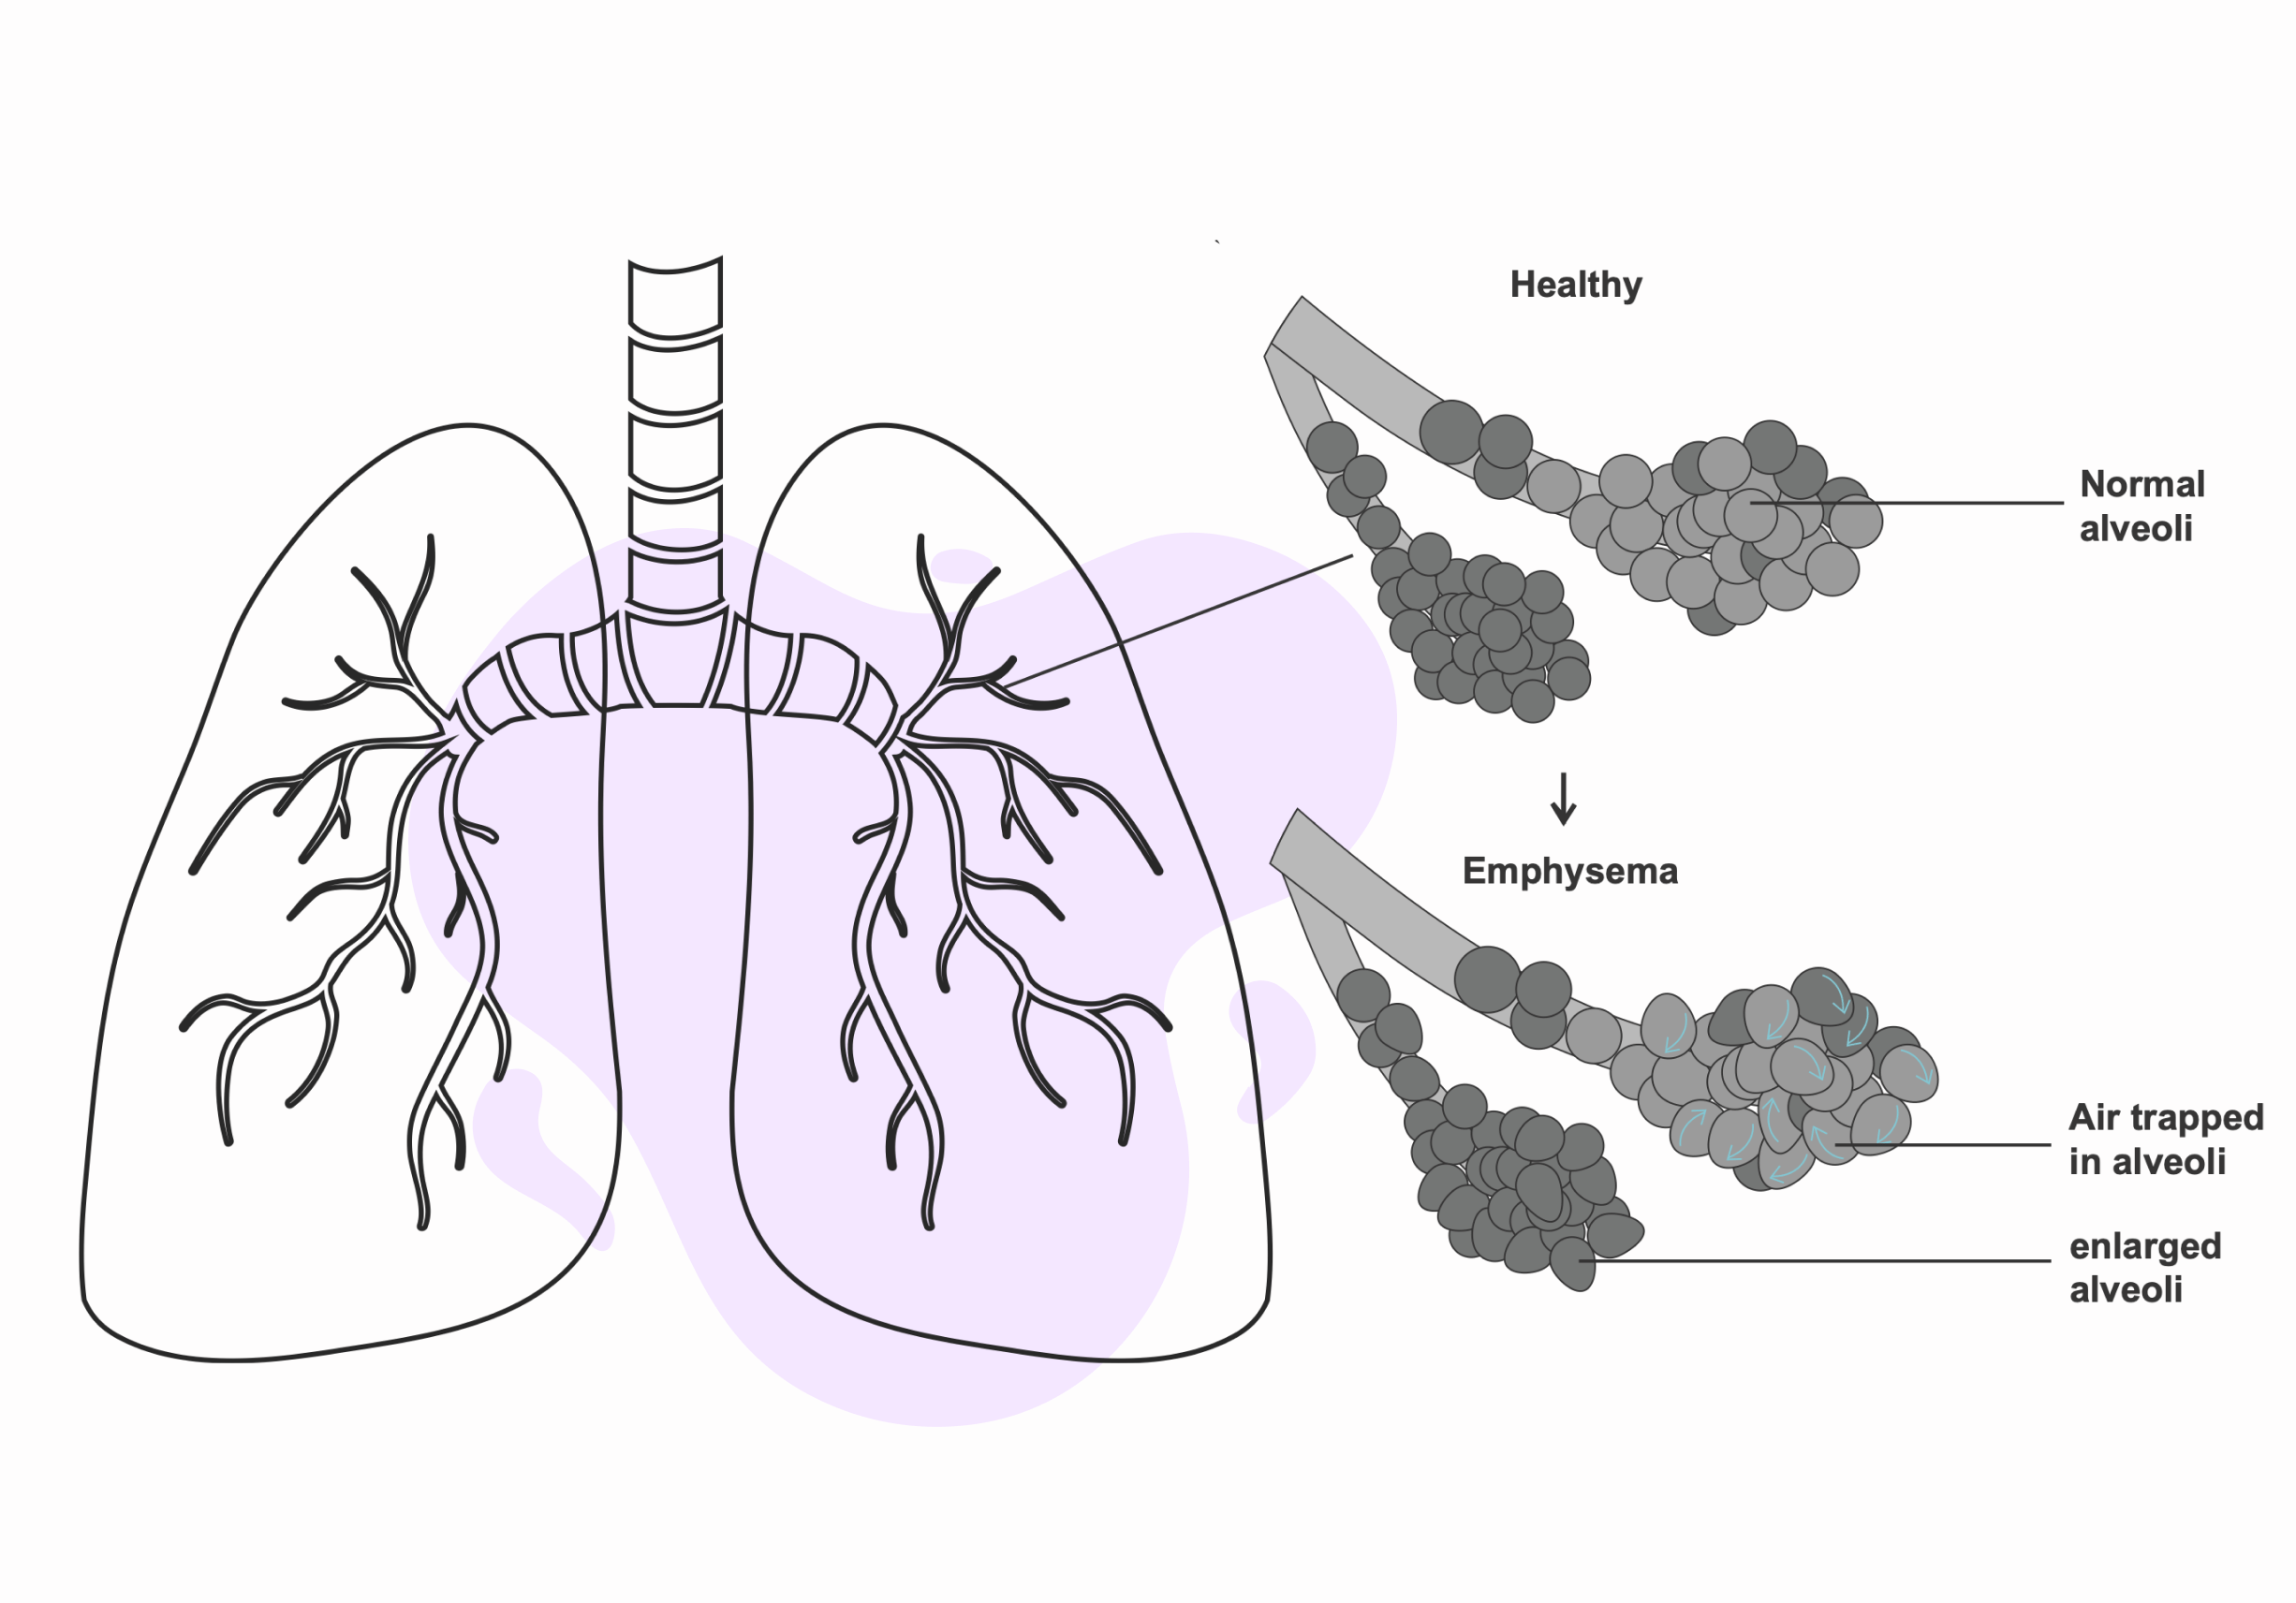

1. Respiratory tract irritation

1. Respiratory tract irritation

Ozone exposure can cause airway constriction. As causing air to become trapped in the alveoli and irritating the respiratory tract.

5. Reduced lung function

Ozone exposure constricts the airways. And it obstructiveness restricts the lungs from functioning normally, reducing lung function.